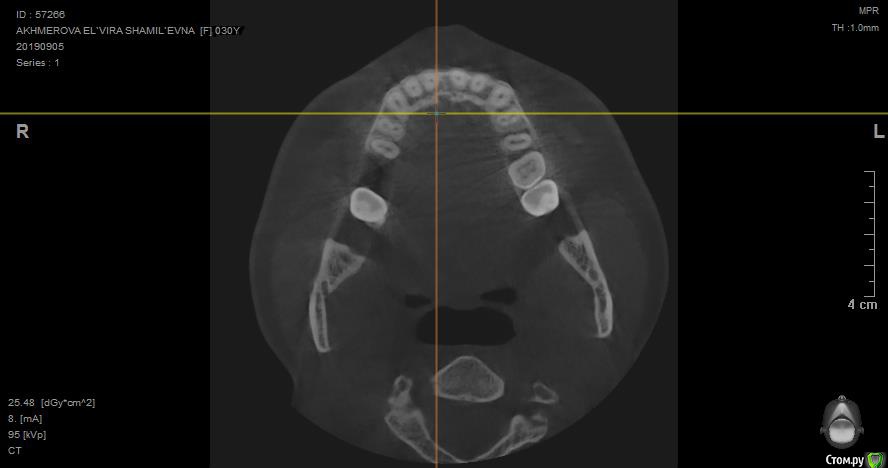

jelly Опубликовано 8 октября, 2019 Поделиться Опубликовано 8 октября, 2019 Добрый день! Посмотрите пожалуйста снимок, верхняя шестерка была удалена вместе с кистой еще в июне, до сих пор с этой стороны тянущая боль, отдающая в висок, шею и лицо. Один из лоров мне сказал, что там в одном месте есть изменения в кости. Подскажите пожалуйста, что делать дальше? Ссылка на снимки кт: https://disk.yandex.ru/client/disk/%D0%9A%D0%A2 Ссылка на комментарий

jelly Опубликовано 8 октября, 2019 Автор Поделиться Опубликовано 8 октября, 2019 КТ после удаления через 2,5 месяца сделано Ссылка на комментарий

jelly Опубликовано 8 октября, 2019 Автор Поделиться Опубликовано 8 октября, 2019 Я не знаю как вам объяснить, наверно это не стоматологическое кт, на срезах видно только челюсть снизу...я не могу найти боковые срезы, как на фотографии. Ссылка на комментарий

Irouil Опубликовано 9 октября, 2019 Поделиться Опубликовано 9 октября, 2019 Судя по всему растёт резидуальная киста. Надо удалять Ссылка на комментарий